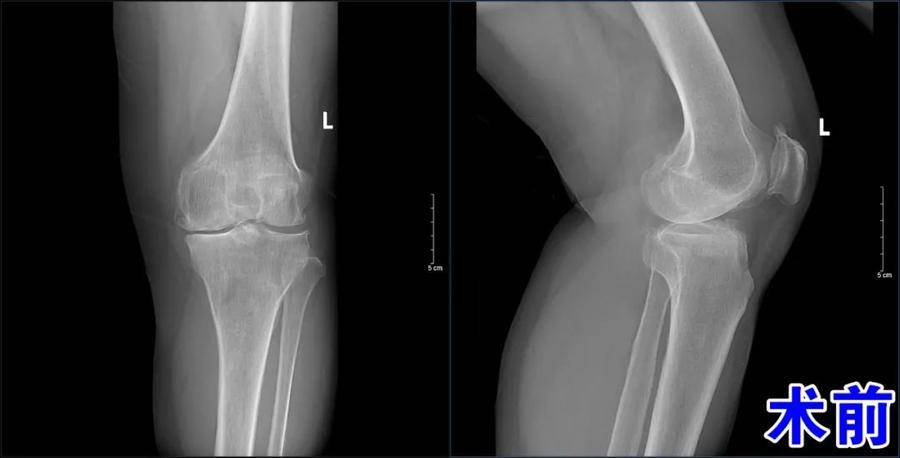

患者在就诊时,已经因为膝关节问题困扰多年。杨学良主任及骨二科团队迅速行动,进行了详细的病例讨论和精准的诊断。对于手术过程,需要考虑到许多细节,确保术后患者能够尽快恢复正常生活。杨主任带领团队,细致地分析患者的病情,制定了一份精确、完善的手术方案。这不仅体现了他们的专业素养,更是对患者生命的尊重和负责。